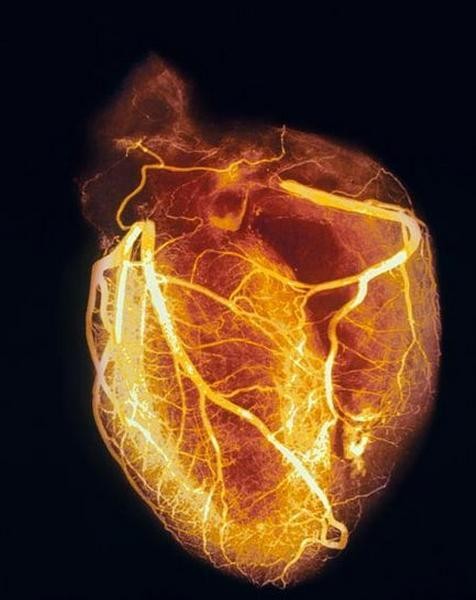

健康心脏显影